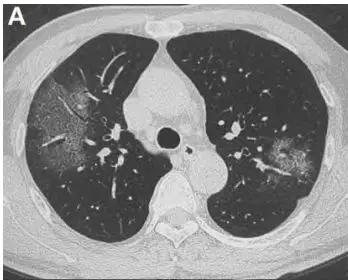

自XXXX年以来,一场突如其来的新冠肺炎疫情席卷全球,这场疫情迅速成为全球共同面临的重大挑战,不仅考验着各国的公共卫生体系和治理能力,也深刻影响着世界格局和人类命运,从最初的局部爆发,到如今在全球范围内蔓延,新冠肺炎已成为这个时代最为引人关注的话题之一。

XXXX年初,新冠肺炎疫情在中国武汉爆发,迅速蔓延至全国,随着病毒传播速度的加快,世界卫生组织于XX月XX日宣布新冠肺炎疫情为国际关注的突发公共卫生事件,此后,各国纷纷加强防控措施,包括限制国际旅行、封锁城市、关闭学校等。